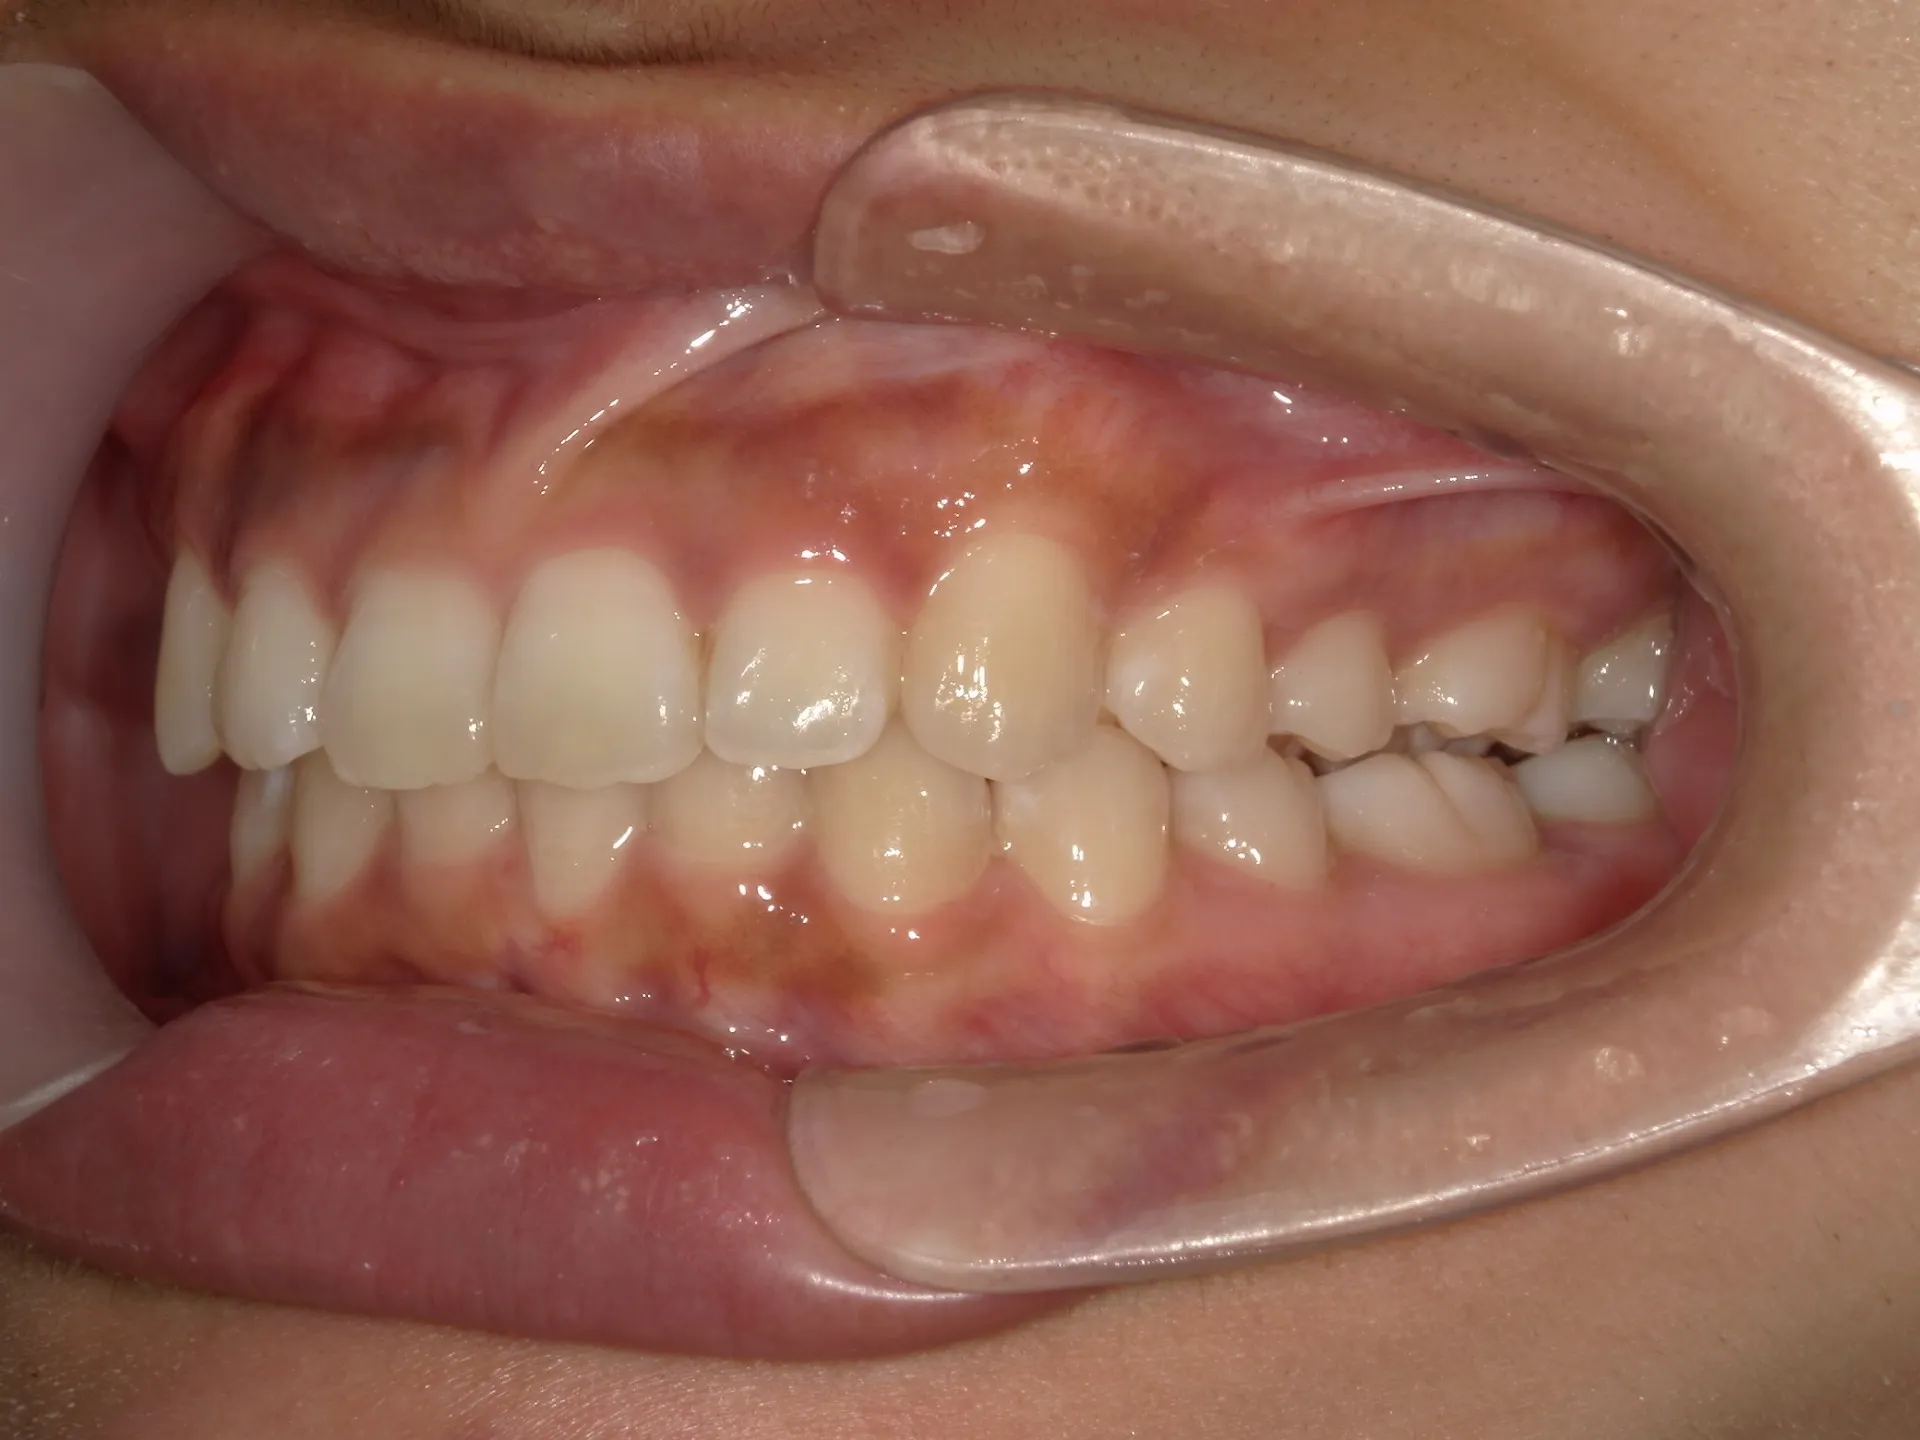

内側に倒れた前歯を矯正で正す!

前歯が内側に倒れてたりしませんか?

または2番目の歯が外側に飛び出していませんか?

この2つはよく同時に起こることがあります。

今回はインビザライン矯正治療(マウスピース矯正)で治療した症例についてご紹介いたします。